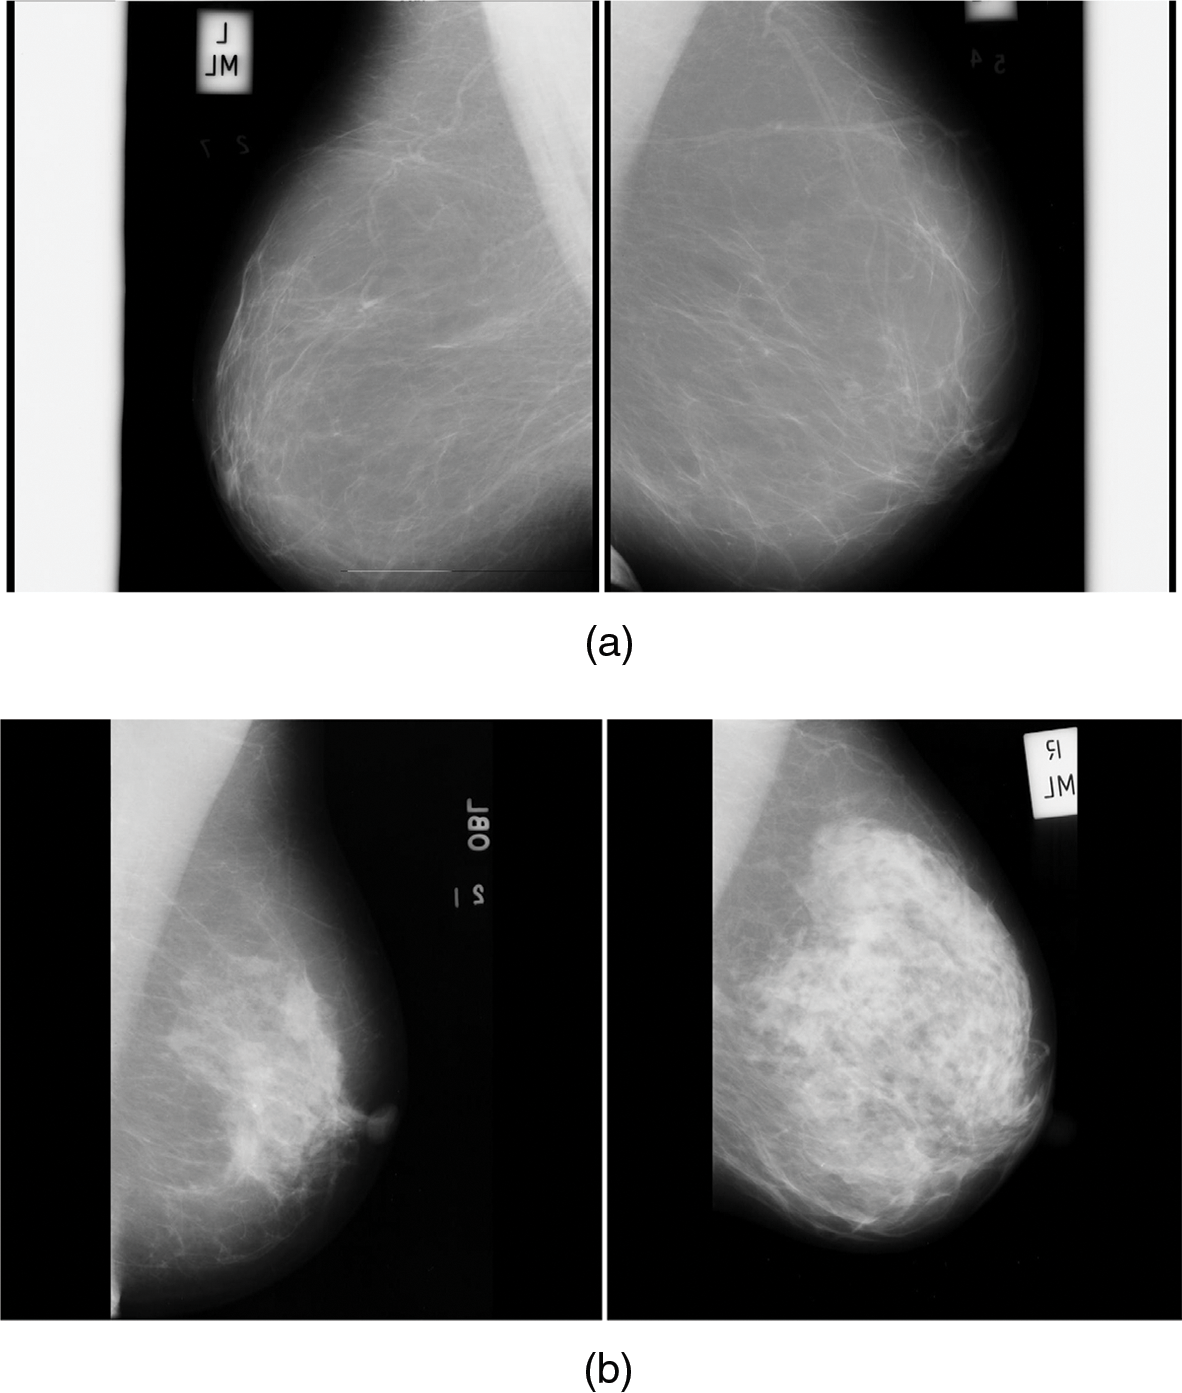

Fig. 6a is the normal mammogram images and Fig. 6b is the abnormal mammogram images.

Figure 6: (a) Normal mammogram images (b) Abnormal mammogram images